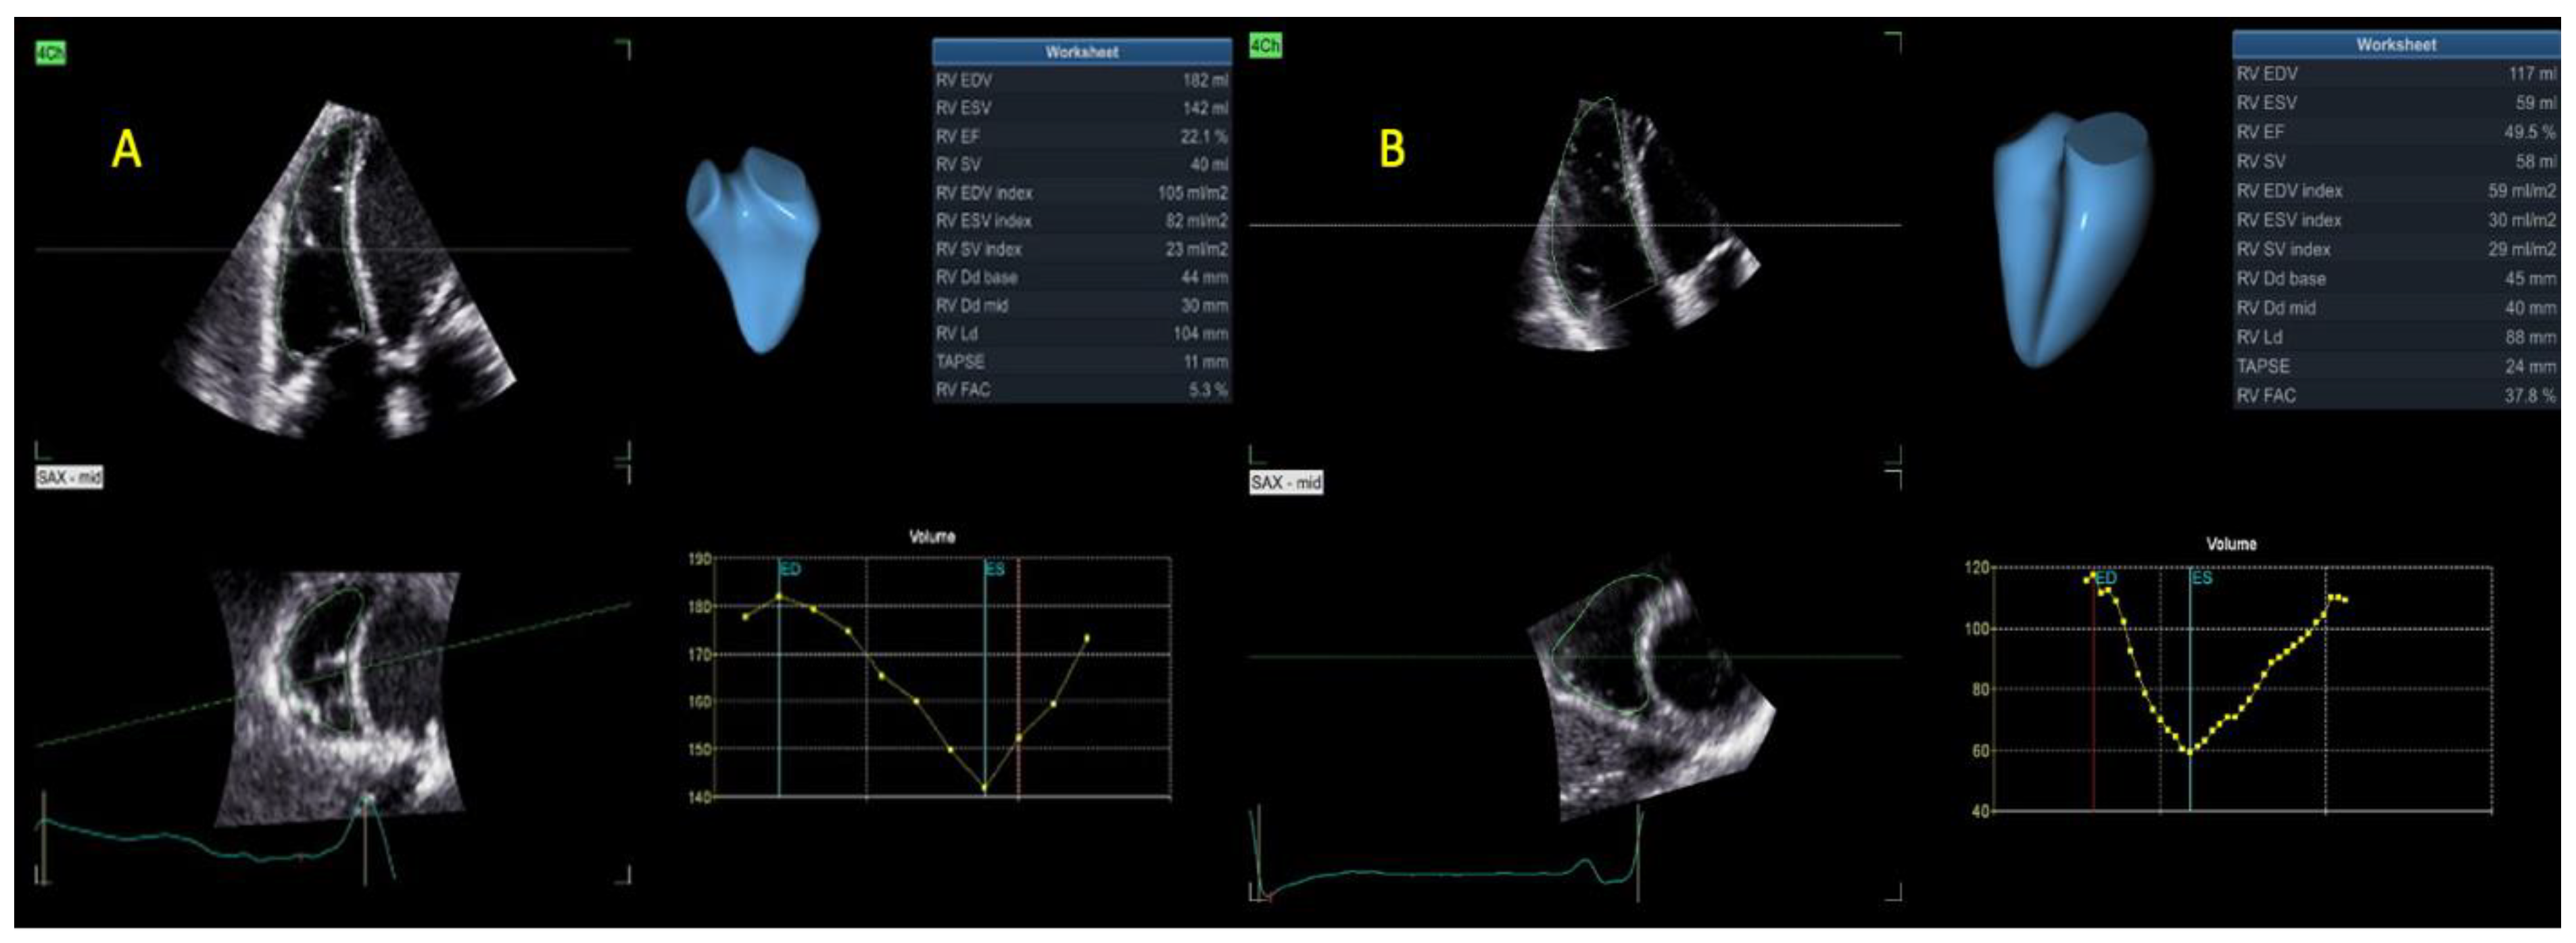

| 3D RVEDV (mL) | 93 ± 47 | 127 ± 59 | 0.01 |

| 3D RVEDV index (mL/m2) | 49 ± 25 | 67 ± 29 | 0.01 |

| 3D RVESV (mL) | 55 ± 35 | 80 ± 44 | 0.01 |

| 3D RVESV index (mL/m2) | 30 ± 19 | 43 ± 21 | 0.01 |

| 3D RVSV (mL) | 38 ± 16 | 47 ± 19 | 0.039 |

| 3D RVEF (%) | 44 ± 10 | 38 ± 8 | 0.03 |